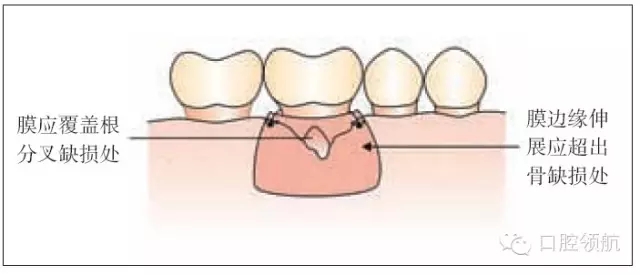

圖26.3 引導(dǎo)組織再生術(shù):膜的放置

引導(dǎo)組織再生術(shù)(GTR)將細(xì)胞的移行重新排序,使來源于牙周韌帶的細(xì)胞能夠增殖并且移行到愈合位點(diǎn),形成新的而非修復(fù)好的牙周膜(圖26.1)。

這項(xiàng)技術(shù)包括膜的放置,它隔開移行的上皮和結(jié)締組織,在清潔的牙根表面創(chuàng)造一個空間。它使細(xì)胞重新附著然后成熟形成新的牙周韌帶纖維,插入到骨組織。

·修剪膜使它大小既能覆蓋缺損同時輕輕延伸超過它的邊緣(圖26.3)。